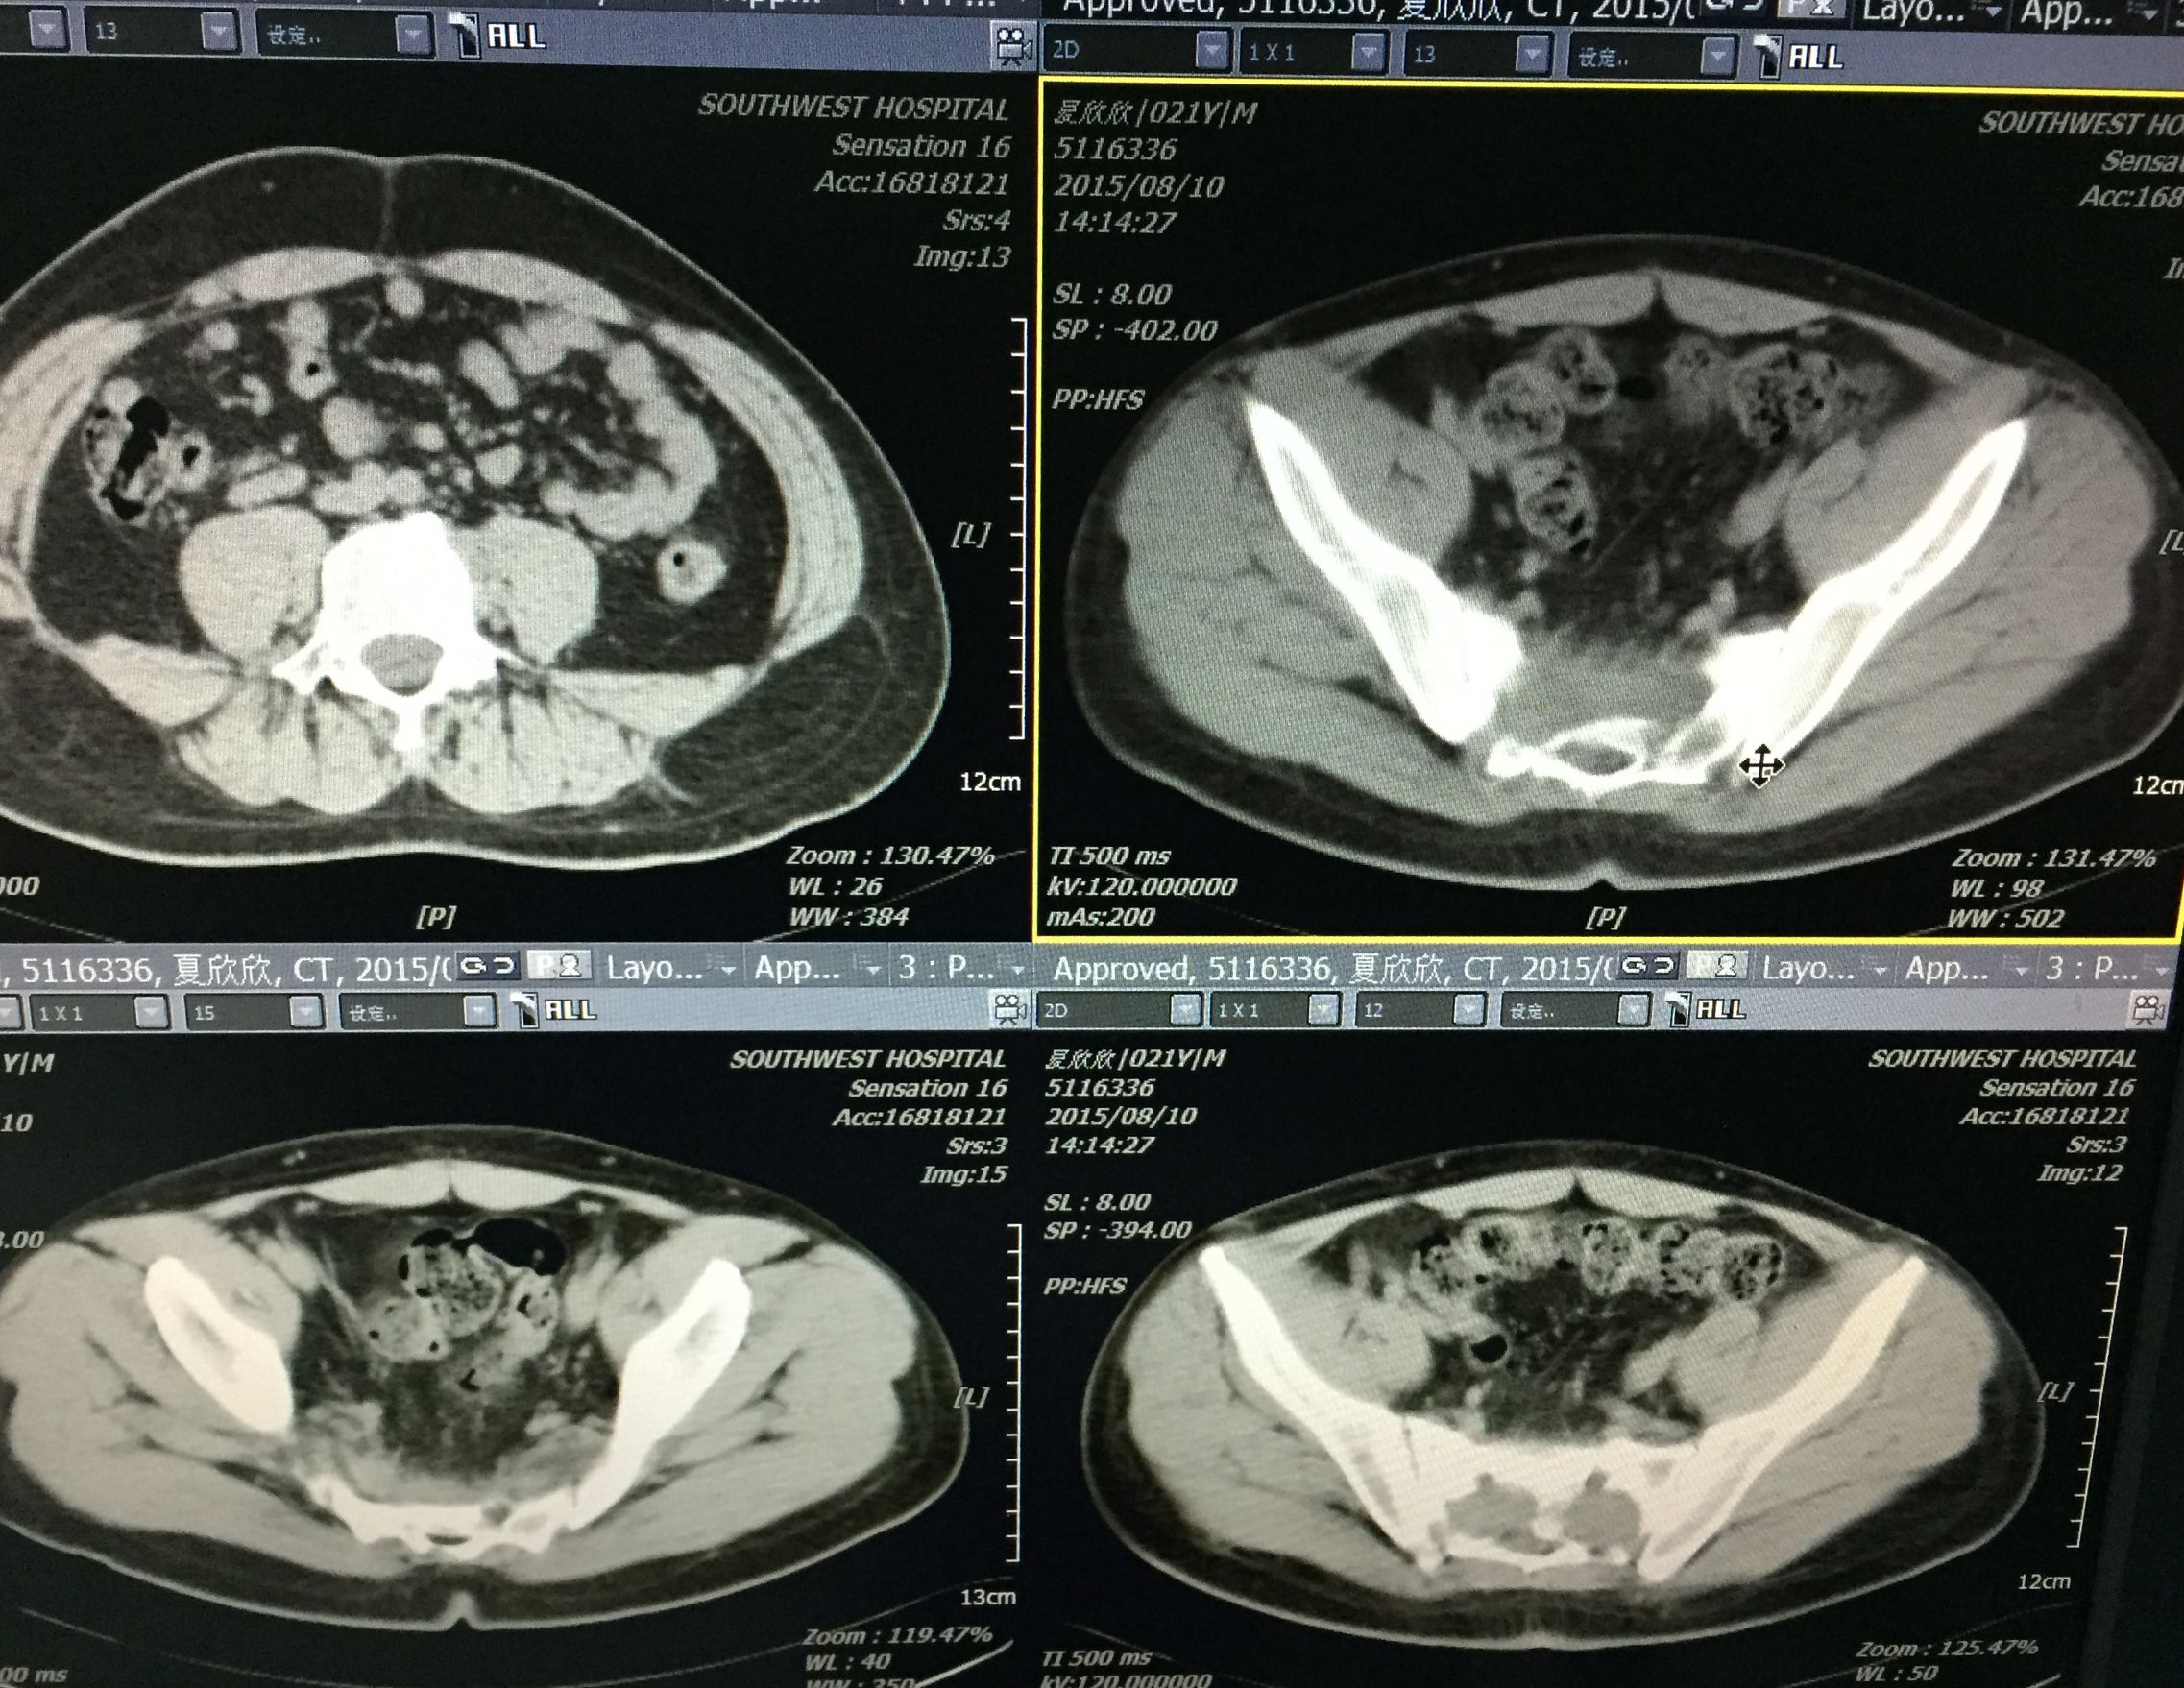

患者 29岁 盆腔及大腿根部多发结核脓肿(如图)

治疗方案充分穿刺置管引流+抗痨治疗

在门诊进行CT引导下穿刺引流术,植入五根引流管(如图白色条状物)

植入一月后,拔出两个引流管,剩余三根引流管仍有脓液溢出。

三月后患者全部拔出引流管。继续抗痨治疗